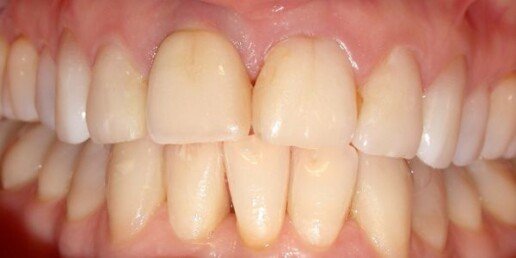

Caso 2

Impianto post-estrattivo immediato e innesto connettivale.

Prima

Dopo